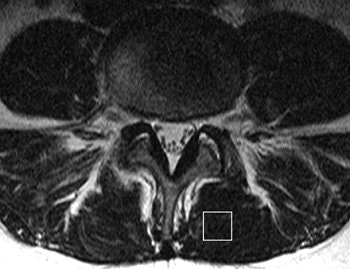

| MR image and corresponding MR spectrum of left multifidus muscle in a symptomatic 36-year-old woman. Above, transverse T2-weighted fast spin-echo MR image (4000/122) at left multifidus muscle (square represents voxel location) at L4-5. At semiquantitative analysis, fatty atrophy was graded 0 (no intramuscular fat). Below, MR spectrum (1500/135) reveals elevated lipid peak (L) with 24.7% fat content (mean value of asymptomatic patients, 14.5%). W = water peak. |

According to the MRS results, the mean percentage fat content of the multifidus muscle was 23.6% for the LBP patients and 14.5% for the volunteers. The mean percentage fat content of the longissimus muscle was 29.3% for the LBP patients versus 26% for the control group.

"In our study, patients with chronic LBP had a significantly larger percentage of fat content in the multifidus muscle when compared with that of the asymptomatic volunteers, but there was no significant difference in percentage fat content for the longissimus muscle," the group wrote. In addition, "this significant difference for the multifidus muscle could not be detected with a semiquantitative grading system...."